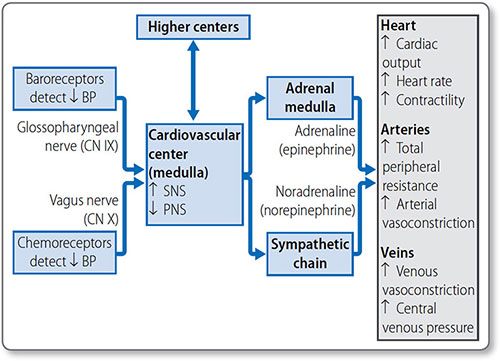

Autonomic control of the heart

The cardiovascular center is a collection of nuclei in the medulla oblongata, and is the branch of the ANS responsible for cardiovascular homeostasis and control. It receives sensory input from peripheral chemo- and baroreceptors, and higher control from the thalamus, hypothalamus and cerebral cortex (Figure 1.28). Through its modulated output it regulates:

- Heart rate (see page 47)

- Cardiomyocyte contractility (see page 46)

- Global blood flow (see page 49)

- Blood pressure (see page 58).

The sympathetic nervous system

Sympathetic signals are transmitted from pre-ganglionic neurons in the lateral thoracic and lumbar spinal cord (levels T1–L2). These synapse with post-ganglionic neurons within the right and left paravertebral ganglia (the sympathetic chains).

Sympathetic nerves innervate the atrial and ventricular myocardium, SA node, AV node and conduction tissues. They release noradrenaline (norepinephrine), which – along with adrenaline (epinephrine) in the bloodstream – activates β1 adrenoreceptors in the heart.

Figure 1.28: The cardiovascular center of the medulla is responsible for the global control of heart rate, contractility and stroke volume, as well as vascular tone, the core determinant of blood pressure.

Control of blood pressure

Blood pressure is regulated in the short term by the cardiovascular center of the ANS (Table 1.15). TPR is also affected by blood vessel autoregulation (see page 51) and the influence of hormones and vasoactive chemicals. Long-term regulation is via hormonal control of blood volume and vascular tone.

Short-term control

The medullary cardiovascular center co-ordinates fast homeostatic mechanisms to ensure tissues have sufficient O2, glucose and other essential metabolites (Figure 1.36).

Figure 1.36: Short-term mechanisms of blood pressure control. A decrease in blood pressure is detected by baroreceptors and chemoreceptors. The cardiovascular center coordinates the response through activation of the sympathetic nervous system (SNS) and inhibition of the parasympathetic nervous system (PNS) to cause a compensatory increase in blood pressure.

Baroreceptors Stretch receptors of the aortic arch and carotid sinus send signals to the cardiovascular center via cranial nerves IX and X. An increase in the rate of baroreceptor action potential firing stimulates the PNS, and inhibits the SNS, to decrease blood pressure. A decrease in pressure has the opposite effect. This baroreflex system is rapid and modifiable (e.g. to accommodate exercise) but doesn't affect long-term control.

Chemoreceptors Chemoreceptors of the aortic arch and carotid bodies are sensitive to changes in blood O2, CO2 and pH. Their signals also travel in the IX and X cranial nerves to the medulla. They have a greater effect on the respiratory than the cardiovascular center.

60Chemoreceptors are activated by decreased O2 and pH and increased CO2, and cause an increase in vascular tone and decrease in heart rate. The bradycardic effect is concurrently overridden by sympathetic stimulation due to lung stretch receptor activation, so that the overall effect is an increase in heart rate, vascular tone and blood pressure.